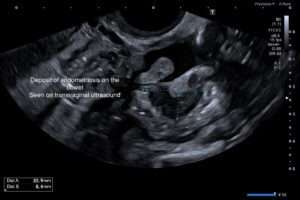

Transvaginal ultrasound (TVUS) is a valuable tool for the diagnosis and staging of endometriosis. The 2022 update of the European Society of Human Reproduction and Embryology (ESHRE) guidelines for diagnosis and management of endometriosis suggests that laparoscopy should no longer be considered the gold standard in diagnosis, favouring imaging as the first-line investigation.

An endometriosis is a complex scan comprising of a consultation, the scan itself and a detailed consultant report.

Click to read the ESHRE Guidelines